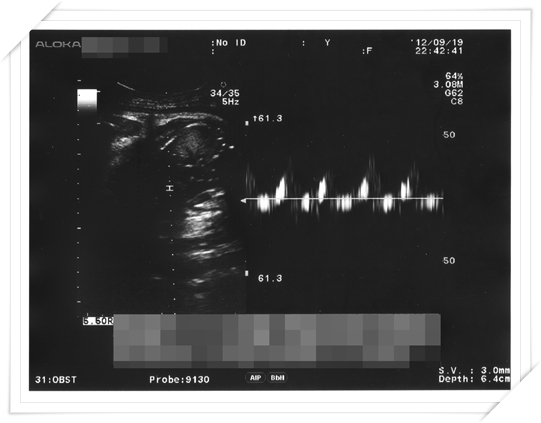

然後這週又碰到了例行產檢啦!!

晚上去產檢的時候 跟醫生說了那天早上發生的事情

還好 看超音波 一切都很正常 小鴨的活動力也還很強

羊水甚麼量也都還很足夠

算是虛驚一場啦!

然後這天產檢呢 才過了兩個星期 小鴨的體重又增加了500g

來到了兩千八啦~~~~~

醫生就一直說“可以生啦可以生啦~~~~ 趕快生一生你就解脫了!”